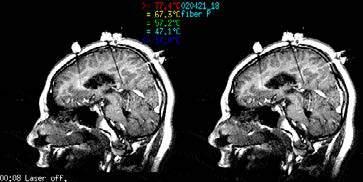

ماظن يف ةيبطلا